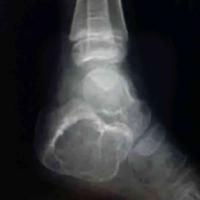

跟骨囊肿

查看图片需登陆

跟骨囊肿...

由 medjpg 发表于 2026-03-24 22:32